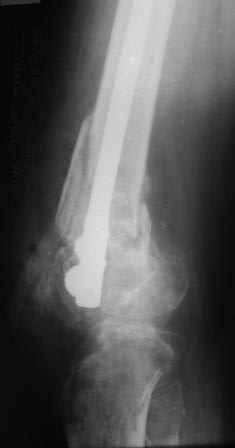

У парня во вложении была контрактура с пателло-феморальным синостозом.

Удалось дополнительно удлинить бедро.